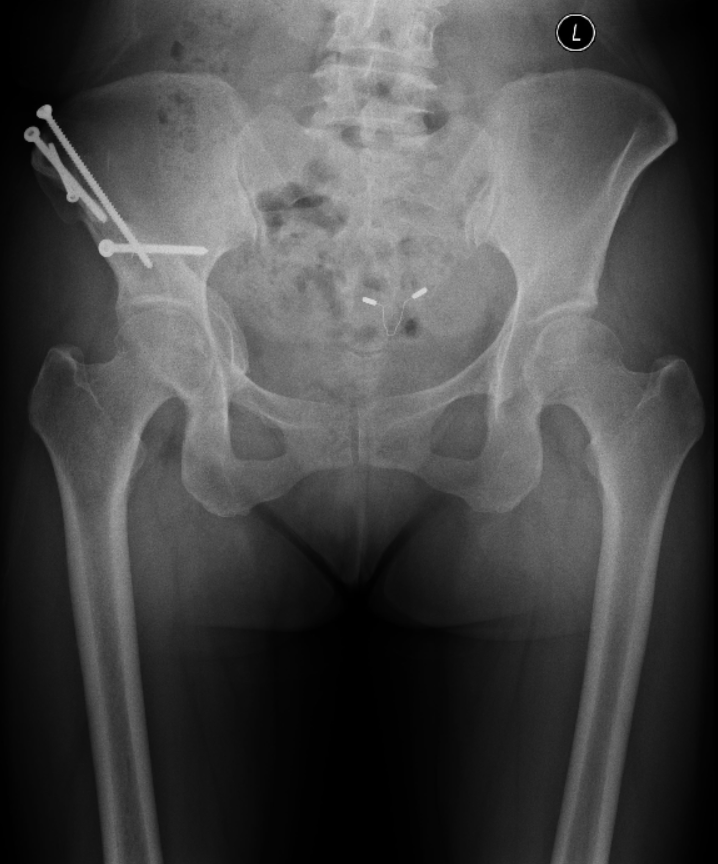

2018-11 术前:双髋关节正位X线片

2020-01 术前:双髋关节正位X线片